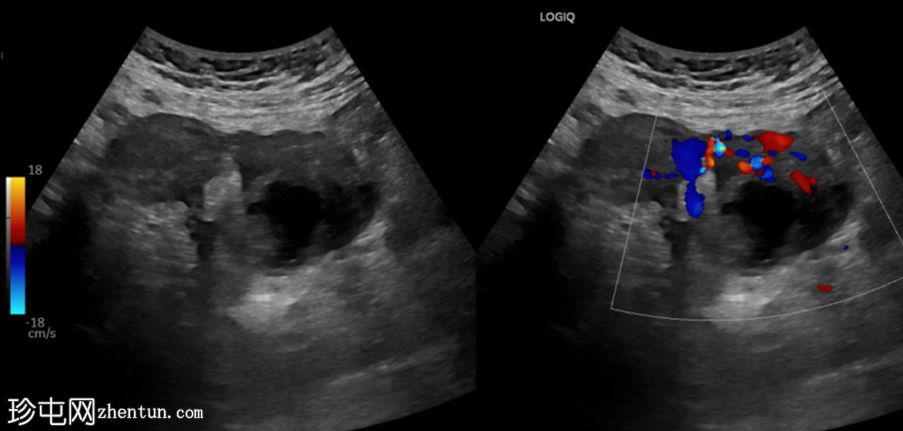

纵切面

左侧卵巢明显增大,可见一囊肿,大小约3.2 x 2.3 cm,呈火环征,可能为黄体囊肿。左侧卵巢与子宫之间可见一管状结构,直径约1.3 cm,内含浑浊液体,未见血管,最可能为输卵管积血。以上特征提示可能为左侧异位妊娠。

未见宫内妊娠囊。